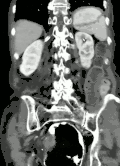

| Coronal CT of the abdomen, demonstrating a volvulus as indicated by twisting of the bowel stock | |